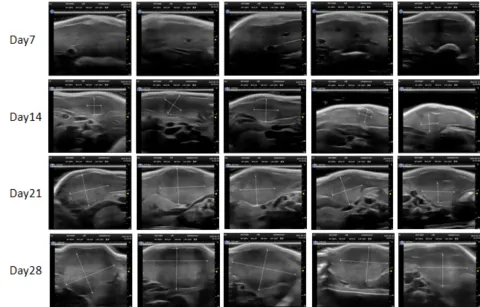

PDX Model (Growth Curve)

部分beats365PDX原位模型展示